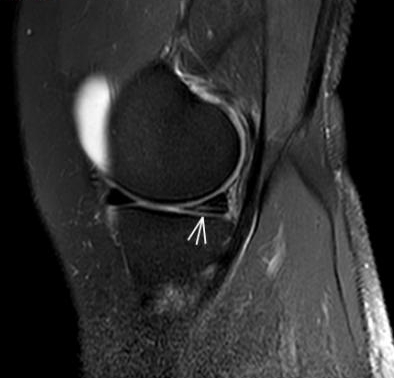

3. 上下樓“針刺痛”——軟骨的“磨砂紙預(yù)警”

場景:爬樓梯時(shí)膝蓋刺痛,久坐后僵硬如“生銹齒輪”

MRI偵查:發(fā)現(xiàn)軟骨變薄、缺損(早期骨關(guān)節(jié)炎信號),趕在“路面塌方”前修復(fù)

(軟骨損傷)